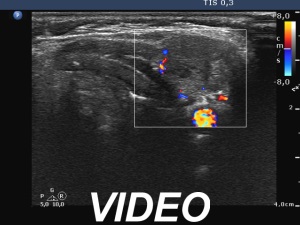

Ultrasonography. There was no thyroid tissue in the thyroid beds. Approximately 7 cm above the thyroid in the left side of the neck there were multiple, moderately hypoechoic lesions which presented tiny cystic areas. They had vascularity but did not have capsule.